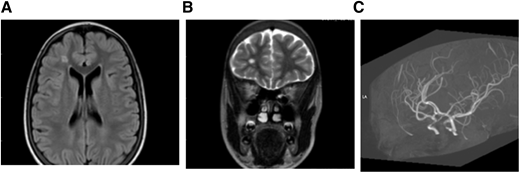

Figure 3.

MRI (A) FLAIR (axial) and (B) T2W (coronal). Brain images from a 15-year-old female with SCA without neurologic complications according to history from parents and child. SCI seen in 2 planes measuring .3 mm in right frontal lobe deep white matter. (C) MRA: right and left cavernous ICA stenosis.

The presence of SCI or stenosis in patients with SCA was identified using MRI techniques on a Philips 1.5 Tesla scanner, including T2-weighted (T2W) MRI, fluid attenuated inversion recovery (FLAIR), and MRA. Representative images are shown in Figures 2 and 3 for 2 sample patients.